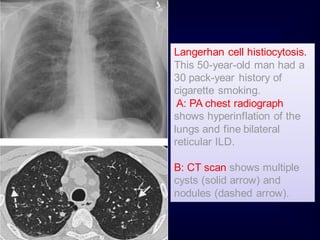

Langerhan cell histiocytosis.

This 50-year-old man had a

30 pack-year history of

cigarette smoking.

A: PA chest radiograph

shows hyperinflation of the

lungs and fine bilateral

reticular ILD.

B: CT scan shows multiple

cysts (solid arrow) and

nodules (dashed arrow).